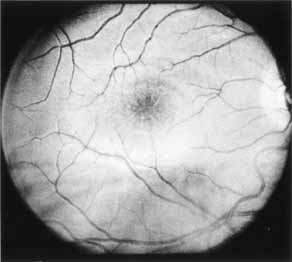

Although there is no reported genetic heterogeneity, there is wide phenotypic variation within the disorder. The major finding within the macula is a classic radial cystic maculopathy. Although retinal signs have been described in infants as young as 3 months, foveal schisis may be difficult to detect, leading to underdiagnosis. The diagnosis is usually not made until the affected male reaches school age (4 to 8 years of age) and encounters visual problems secondary to foveal involvement. Typical foveal schisis findings have been reported in 68% to 100% of eyes within various series.37,38 Foveal schisis is the only finding in about half the cases. It is characterized by the presence of radiate perifoveal microcysts located in the nerve fiber layer (Fig. 1) with radiate plications of the overlying internal limiting membrane that are seen especially well on monochromatic (red-free) photography (Fig. 2). The microcystoid change may slowly progress to form a macular cyst or hole. Foveal schisis has been reported in association with Goldmann-Favre vitreotapetoretinal dystrophy and rarely may be seen in rod-cone dystrophy or as an autosomal dominant or recessive condition.39–43